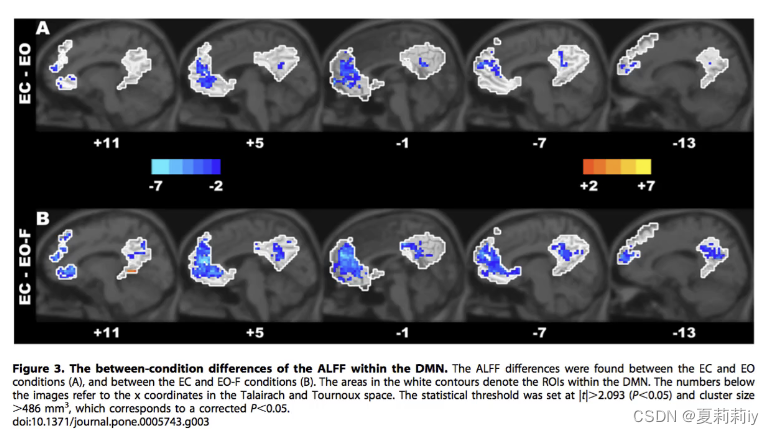

①可以看看患者和普通人ALFF的图像差异

③生成的结果示例

(5)Paired T-Test

①对同一个被试的重复测量,此图是同一被试睁眼闭眼的图像

②被试内设计具有很高的说服力,因为排除了组间差异。因此在小样本分析时,尽量用被试内分析